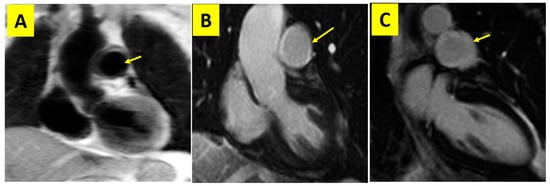

- Aortic aneurysms and aortic dissection: extracted from the patient’s computed tomography angiography (CTA) reports;

- Main pulmonary artery aneurysms: registered based on the patient’s CTA and CMR findings.

- Yang, J.; Peng, M.; Shi, J.; Zheng, W.; Yu, X. Pulmonary artery involvement in Takayasu’s arteritis: Diagnosis before pulmonary hypertension. BMC Pulm. Med. 2019, 19, 225. [Google Scholar] [CrossRef] [PubMed]

- Xi, X.; Du, J.; Liu, J.; Zhu, G.; Qi, G.; Pan, L. Pulmonary artery involvement in Takayasu arteritis: A retrospective study in Chinese population. Clin. Rheumatol. 2021, 40, 635–644. [Google Scholar] [CrossRef] [PubMed]

| ACCCMR (%) | DCM | 1 (2.7) | Main PA aneurysm | 1 (2.7) |

| LPA stenosis | 1 (2.7) | Myocarditis | 6 (16.2) | |